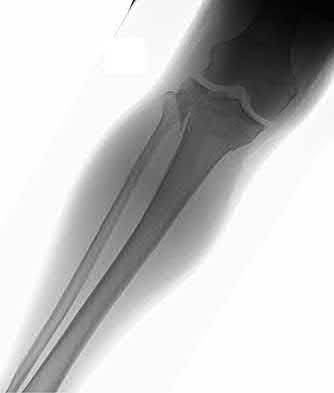

1. # A 32-year-old male sustains the injury shown in Figure A and undergoes treatment as shown in Figure B. Following placement of this implant, what is the best technique to confirm it is not too proud proximally?

The safe zone for tibial nail placement as seen on radiographs is just medial to the lateral tibial spine on the anteroposterior radiograph and immediately adjacent and anterior to the articular surface as visualized on the lateral radiograph.

Tornetta et al specifically located the safe zone for nail entry in a study using fresh frozen cadaver knees. The authors found that the safe zone for nail placement is located 9.1+/-5 millimeters lateral to the midline of the plateau and three millimeters lateral to the center of the tibial tubercle. The width of the safe zone averaged 22.9 millimeters and was as narrow as 12.6 millimeters.

The starting point of the of the nail can be best viewed on the lateral knee radiograph, an example of which is shown in Illustration A. Illustration B shows the "sweet spot" for nail insertion as defined by Tornetta.